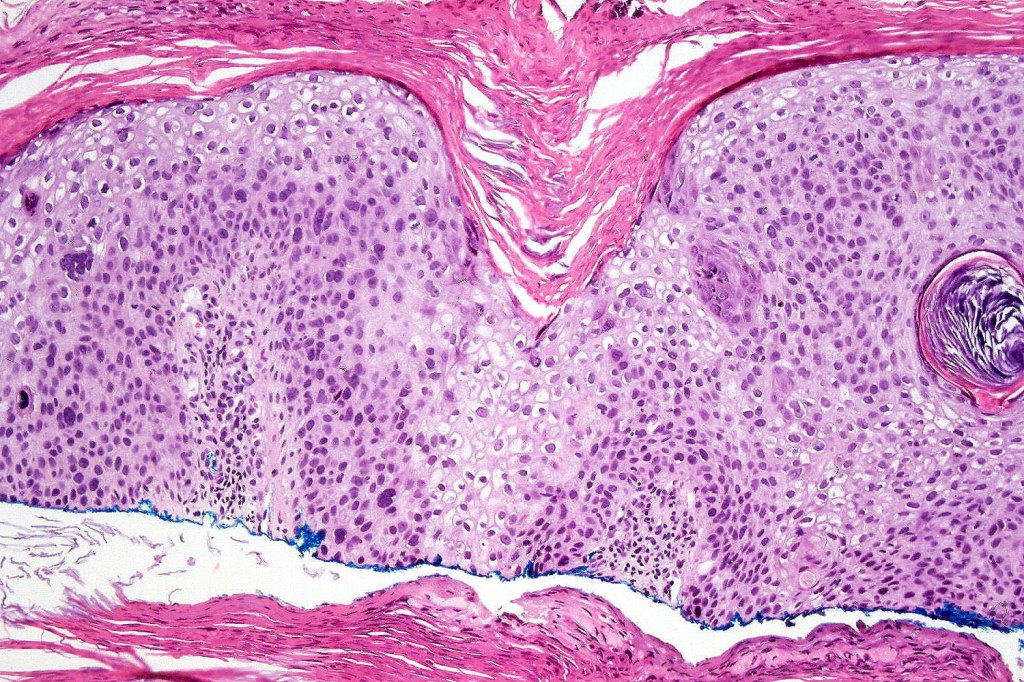

•Hyperkeratosis, parakeratosis & acanthosis

•Full thickness dysplasia (carcinoma in situ) involving the epidermis and intraepidermal adnexal elements

•Loss of maturation, nuclear pleomorphism, marked mitotic activity +/- abnormal forms

•Dyskeratosis & apoptosis